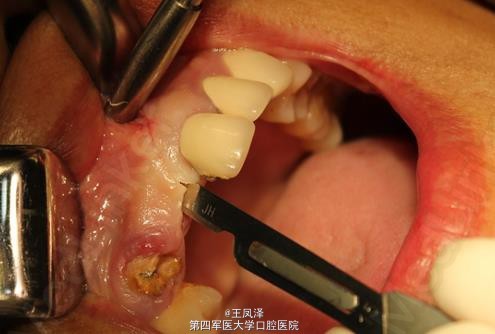

患者女,43岁,5年前在外地做的左上3到右上3烤瓷连冠,具体材料不祥,右上2先天缺失,右上3基牙已全部腐蚀掉。

X光见右上3残根仅有7mm长,用砂片从左上1和右上1之间分开。患者要求种植牙。